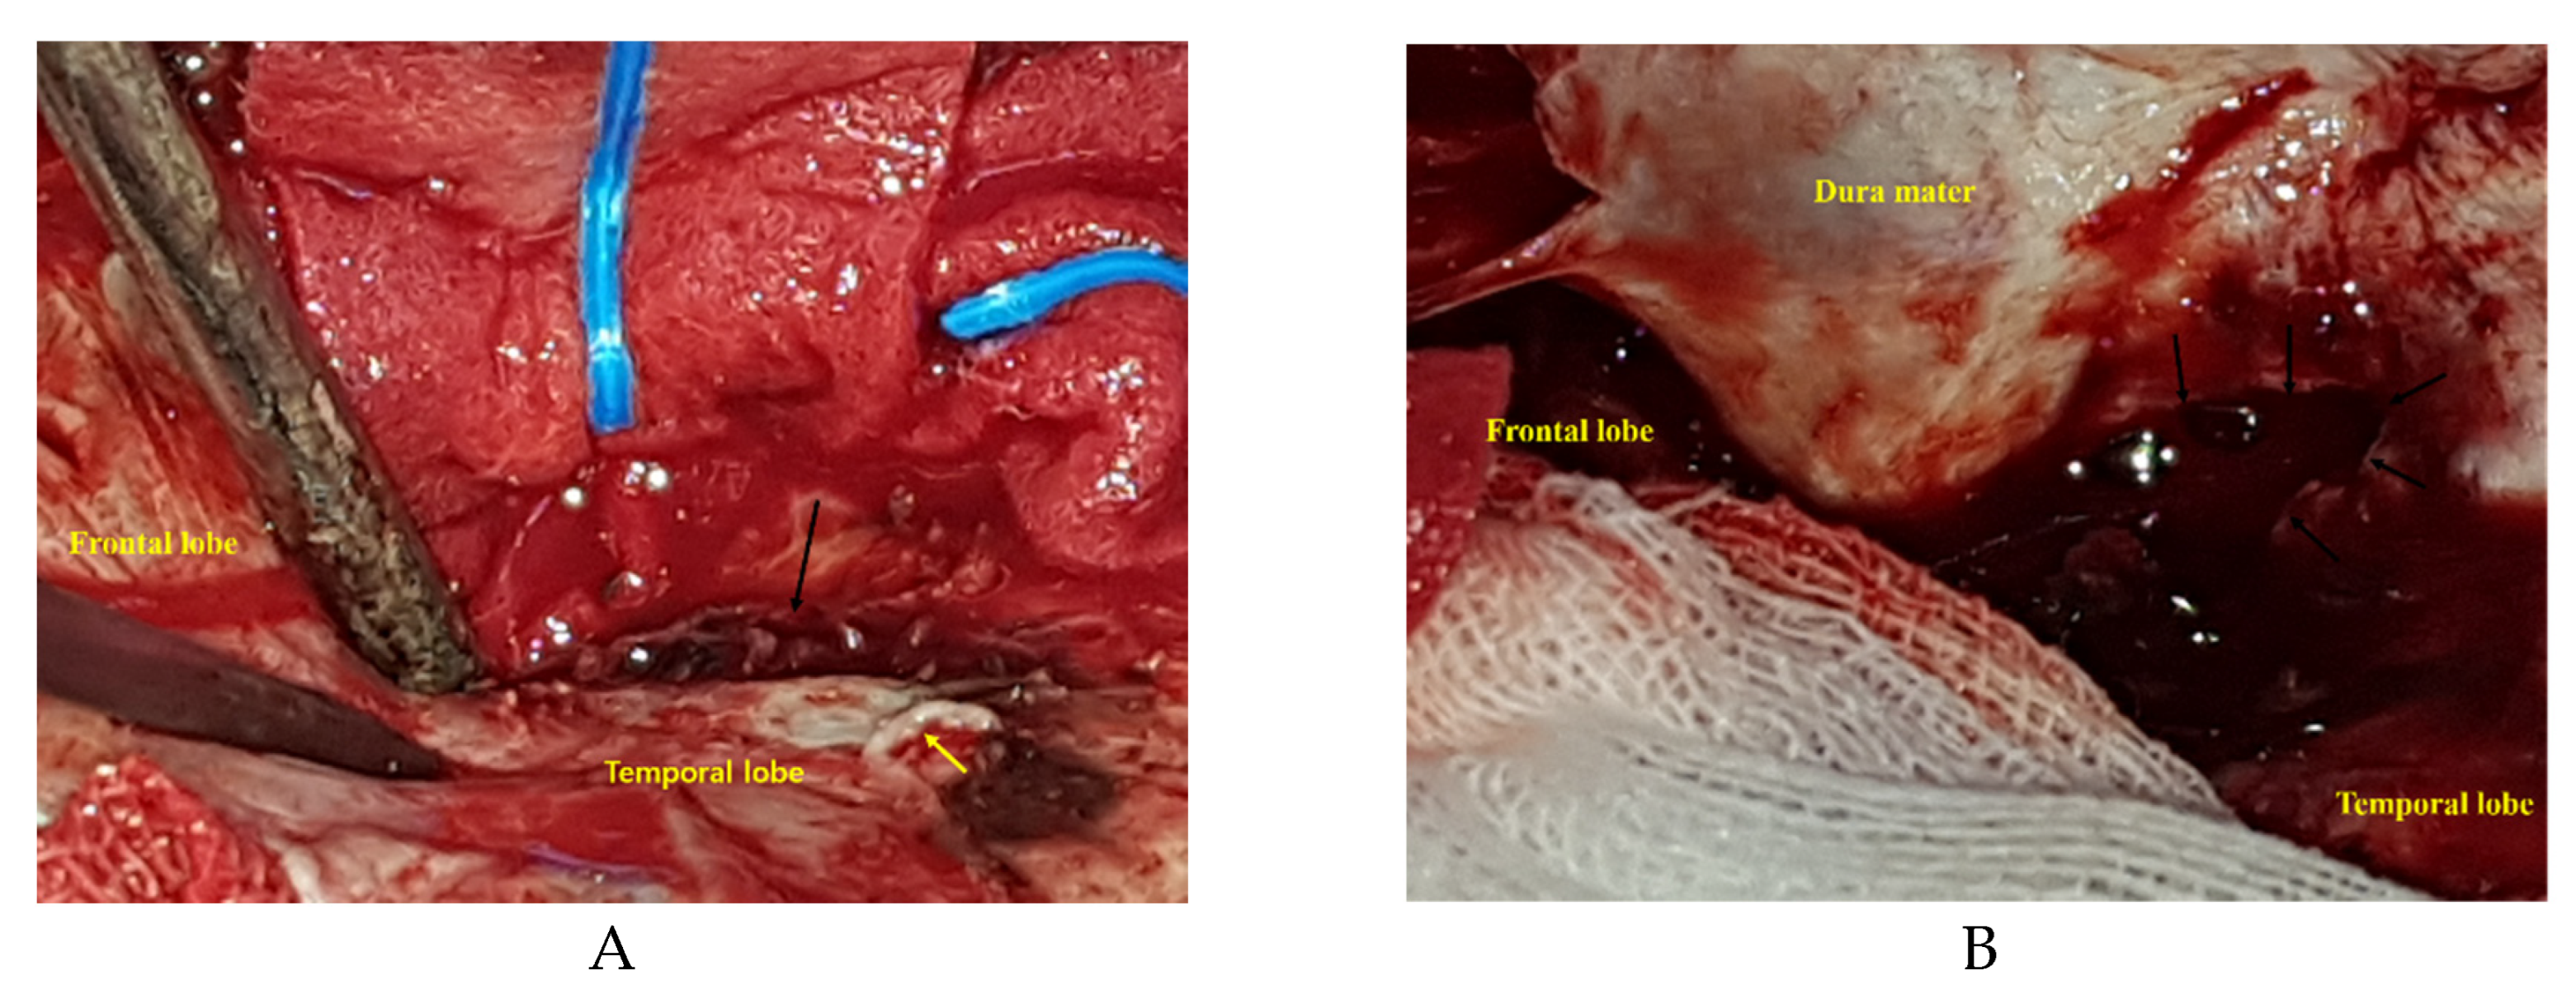

In both reports, the authors mentioned that brisk epidural bleeding during bone flap removal and dura tear were detected. Moon et al., proposed that a rupture of a pseudoaneurysm rupture in the MMA contacting with a dural defect could cause ICH via the dura tear [6] (Figure 2). Figure 1 and Figure 2 demonstrate that rupture of a pseudoaneurysm in the MMA with a dura tear results in small EDH and acute ICH. In situations where there is a dura tear, rupture of a pseudoaneurysm located in the epidural space produces EDH at the initial stage of the rupture and subsequently results in ICH via the dura tear.

In operations of acute ICH for pseudoaneurysm in the MMA, intraoperative rupture just after bone flap removal developed in two patients [6,7]. Moon et al., described a pseudoaneurysm attached to the outer surface of the dura mater accompanied by abrupt bleeding just after bone flap removal [6]. Kumar et al., also reported brisk extradural bleeding after bone flap removal [7].

Figure 2. Intraoperative photographs. Dura mater after bone flap removal presents a tear located on the right temporal side (A, yellow arrow: middle meningeal artery [MMA] after removal of pseudoaneurysm and coagulation of proximal MMA, black arrow: dura tear). The MMA is originally traversing the site of the dura tear. And removed pseudoaneurysm of MMA is originally located over dura tear. After opening of dura mater, subdural hematoma and intracerebral hemorrhage contacted with dura tear is observed (B, black arrow: dura tear).